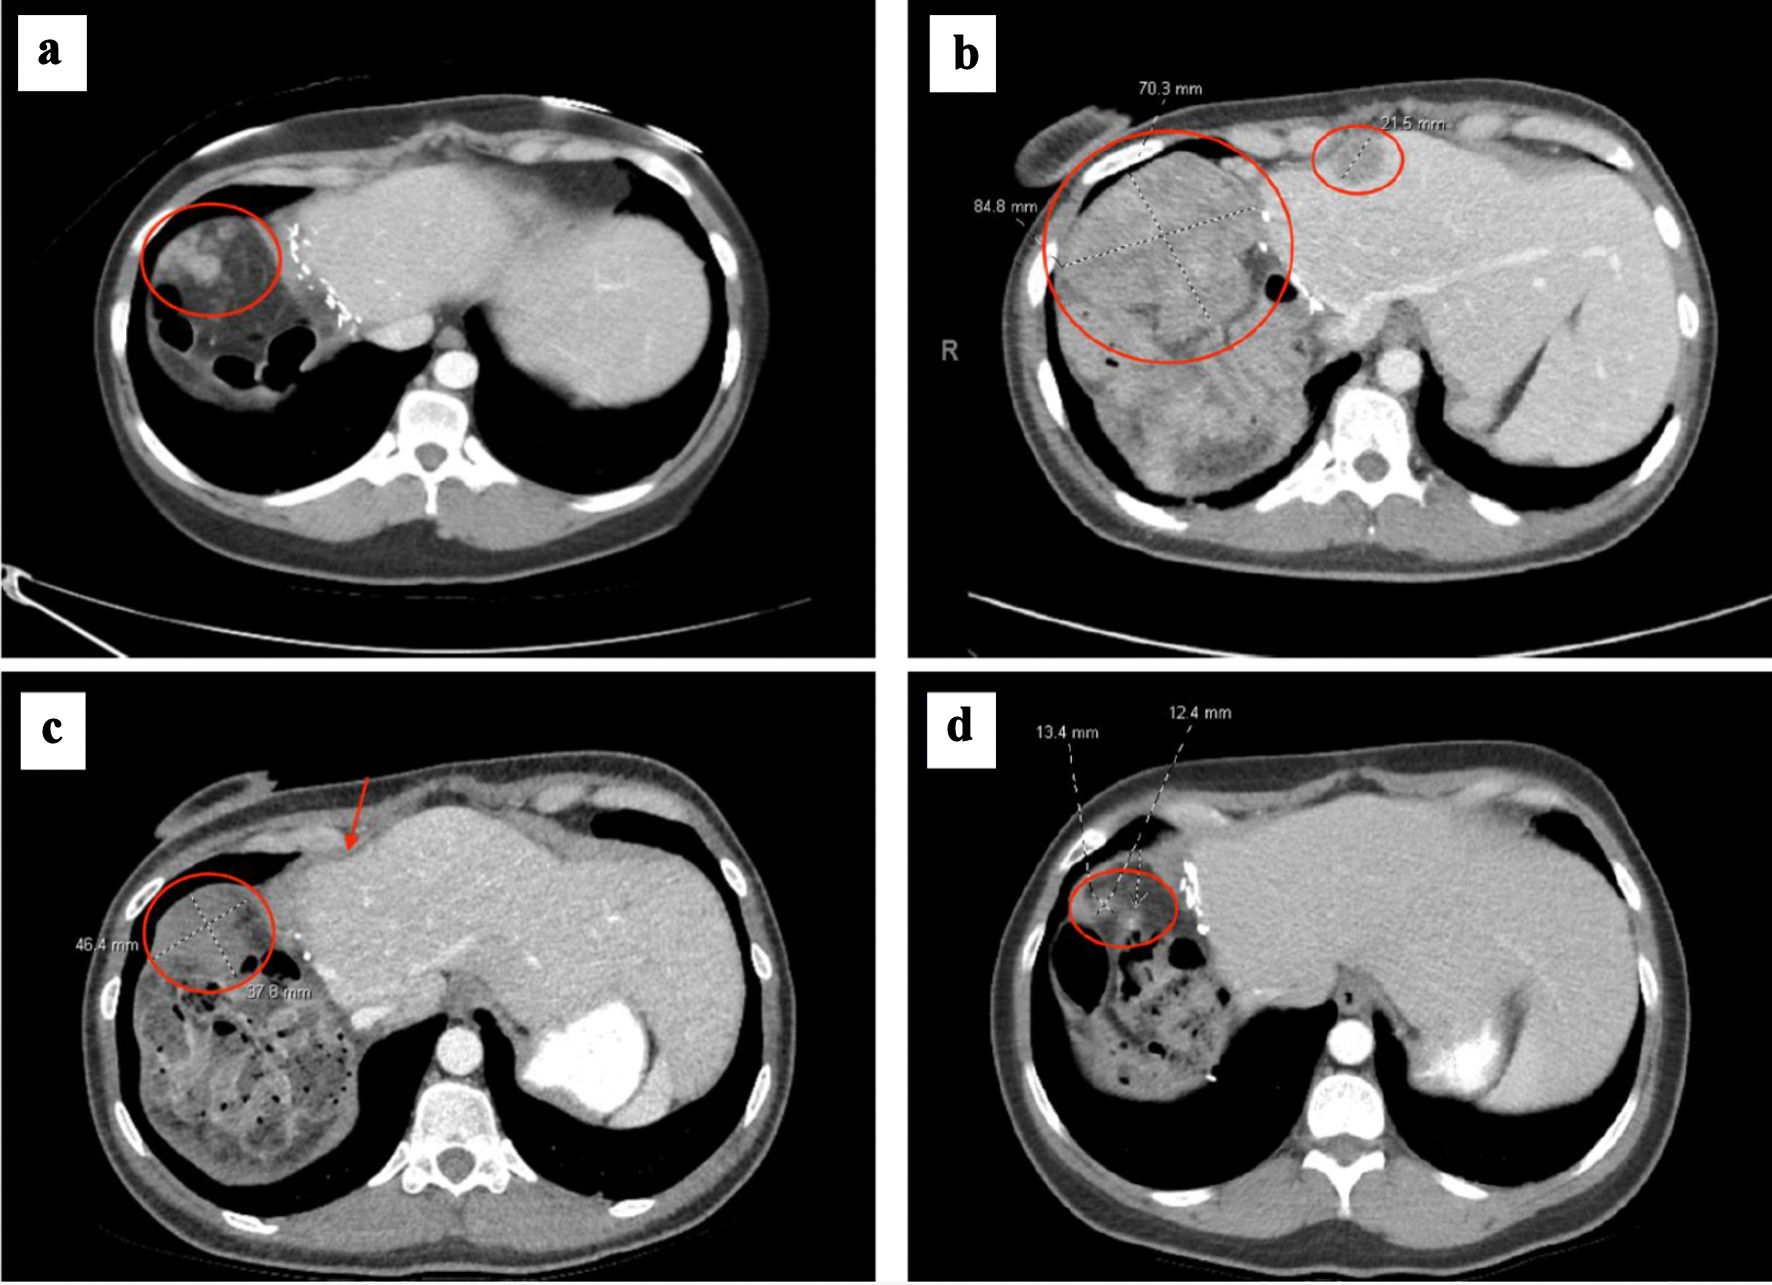

After surgery, her AFP initially reached a nadir of 1,011 ng/mL; however, at 6 weeks postoperatively it increased to 3,962 ng/mL (Fig. 1). She underwent a positron emission tomography-computed tomography (PET/CT) scan, which showed multiple new hypermetabolic peritoneal implants and hypermetabolic retroperitoneal lymph nodes (Fig. 3a). Given these new imaging findings with rising AFP, the overall clinical picture was consistent with rapid disease recurrence. She started treatment with atezolizumab and bevacizumab 2 months postoperatively. Given her untreated HCV, she received concurrent treatment with sofosbuvir/velpatasvir for 12 weeks with sustained virologic response and cure of HCV. After three cycles (2 months) of immunotherapy, repeat CT scans showed significant enlargement of peritoneal metastases (PMs), corresponding with rising AFP to 82,882 ng/mL. Her systemic treatment was then changed to lenvatinib; however, her AFP increased further to 357,321 ng/mL after a month (Fig. 1).

![]() Click for large image | Figure 3. (a) Right upper quadrant peritoneal metastasis (circled) at time of metastatic recurrence after initial hepatectomy. (b) Right upper quadrant peritoneal metastasis (circled) increased to 8.5 cm, which had progressed after no response to atezolizumab/bevacizumab and lenvatinib. Smaller mid-anterior surface perihepatic implant also noted (circled). (c) Right upper quadrant peritoneal metastasis decreased to 4.6 cm (circled) and anterior perihepatic implant (arrow) resolved after 2 months of GEMOX. (d) Right upper quadrant peritoneal metastasis decreased to 1.3 cm prior to cytoreductive surgery and HIPEC, after several months of GEMOX followed by gemcitabine monotherapy. GEMOX: gemcitabine and oxaliplatin; HIPEC: hyperthermic intraperitoneal chemotherapy. |

Postoperatively, she developed worsened abdominal pain, nausea, and vomiting, requiring hospitalization for pain management. Repeat CT imaging demonstrated further disease progression with multiple PMs, with the largest lesion now 8.5 cm (Fig. 3b). Due to continued rapid progression without systemic control of disease, consideration of CRS/HIPEC was withheld. She received a single fraction (8 Gy) of palliative radiation to the large, right abdominal peritoneal metastasis for pain control. She was additionally treated with escalating doses of opioids for pain management. Given lack of response to immunotherapy and anti-angiogenic TKI therapy, and clinical presentation of painful, large tumor burden with preserved liver function, she was started on a cytotoxic chemotherapy with gemcitabine and oxaliplatin (GEMOX) administered every other week. She tolerated chemotherapy well, her abdominal pain began to improve, and she was subsequently discharged from the hospital.

She continued to receive GEMOX and exhibited a rapid decline in AFP to 2,010 ng/mL after 2 months of treatment. Interval CT imaging showed significant reduction in size of peritoneal lesions by nearly 50% (Fig. 3c). By 4 months of chemotherapy, her AFP normalized to 4.3 ng/mL. CT scans showed continued response, with the largest lesion now 3.4 cm. She was then transitioned to gemcitabine monotherapy given cumulative neurotoxicity from oxaliplatin, which included symptoms of peripheral neuropathy and foot drop, the latter of which improved after oxaliplatin was discontinued. Her peritoneal disease continued to improve on CT imaging after 3 more months of gemcitabine, and her AFP remained within normal range. Her cancer-associated pain improved and remained well-controlled with chemotherapy in addition to medical pain management.

With her remarkable response to chemotherapy and peritoneal-only disease on CT imaging and continued normalization of AFP, she underwent further multidisciplinary review. After extensive discussion of risks and benefits, the decision was to incorporate CRS and HIPEC in her disease management to optimize oncologic outcome. After an additional 2 months of gemcitabine monotherapy with continued disease control on imaging (Fig. 3d), she underwent a complete macroscopic tumor cytoreduction (score - CCR 0), which included removing the disease-bearing omentum, right upper quadrant parietal peritoneum, right and left anterior peritoneum, transverse mesocolon peritoneal implants, total abdominal hysterectomy, bilateral salpingo-oophorectomy, followed by HIPEC with mitomycin-C (MMC) and cisplatin for a calculated total PCI of 10. HIPEC with 40 mg of MMC was employed over the entire 90-min perfusion period that included 126 mg of cisplatin delivered during the latter 60 min.